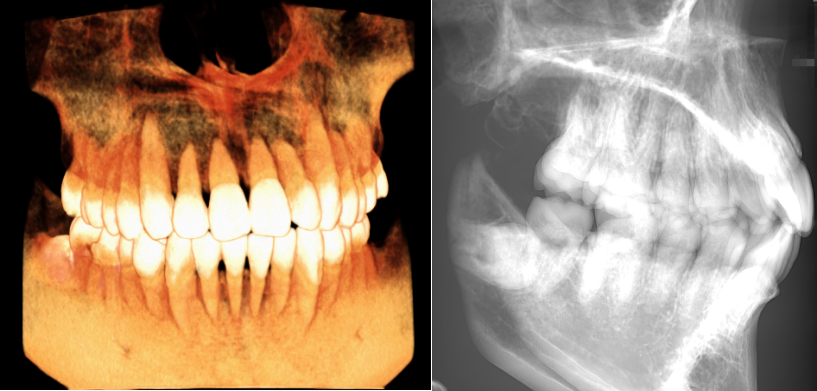

▲大视野图像

大视野可覆盖大部分头颅颌面,显示从上颌到下颌及双侧颞颌关节的完整形态适用于上下颌全牙列、颌面外科、全口种植以及正畸正颌等领域的临床应用。